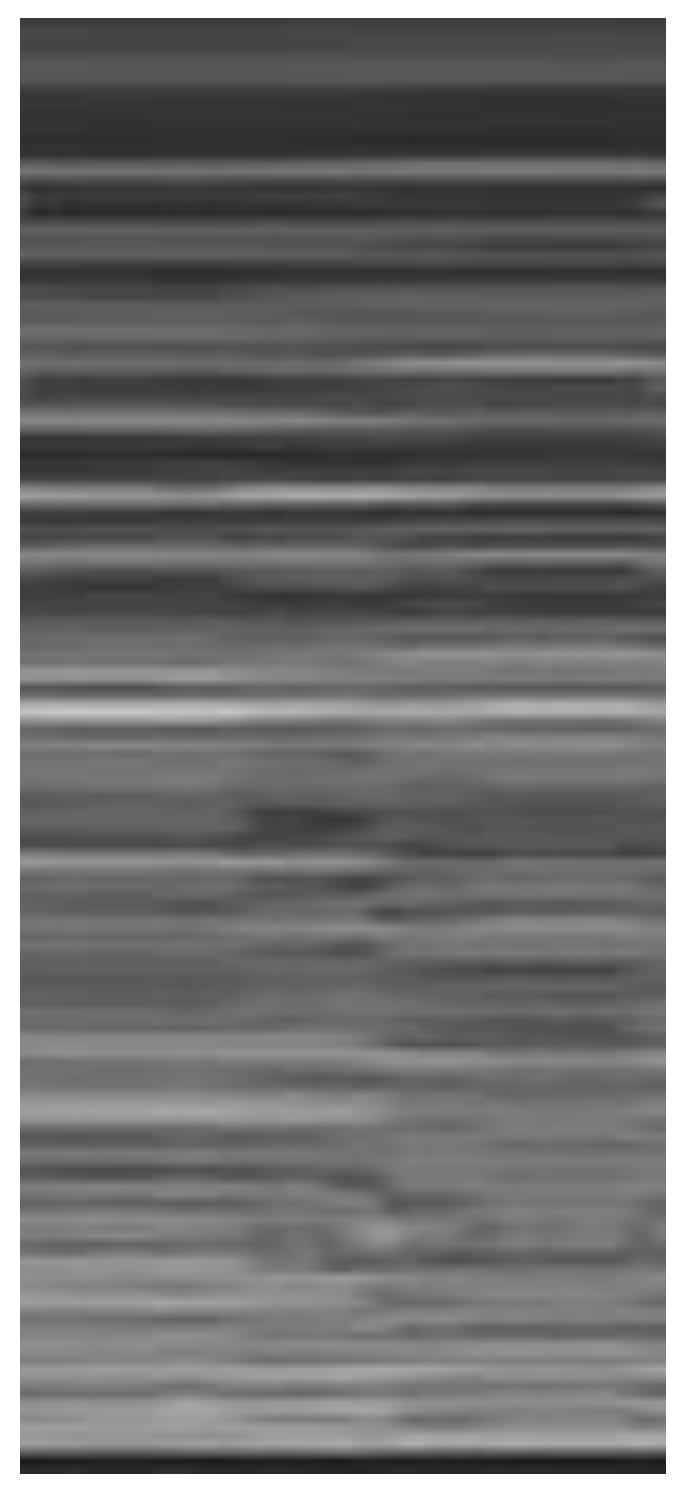

| Seashore sign (Figure 5) | The pleura is represented by horizontal artifacts and the underlying lung has a sandy pattern. | Normal finding |

| Barcode sign (sign of the stratosphere) (Figure 6) | Both the pleura and the lung appear as horizontal artifacts | PNX |